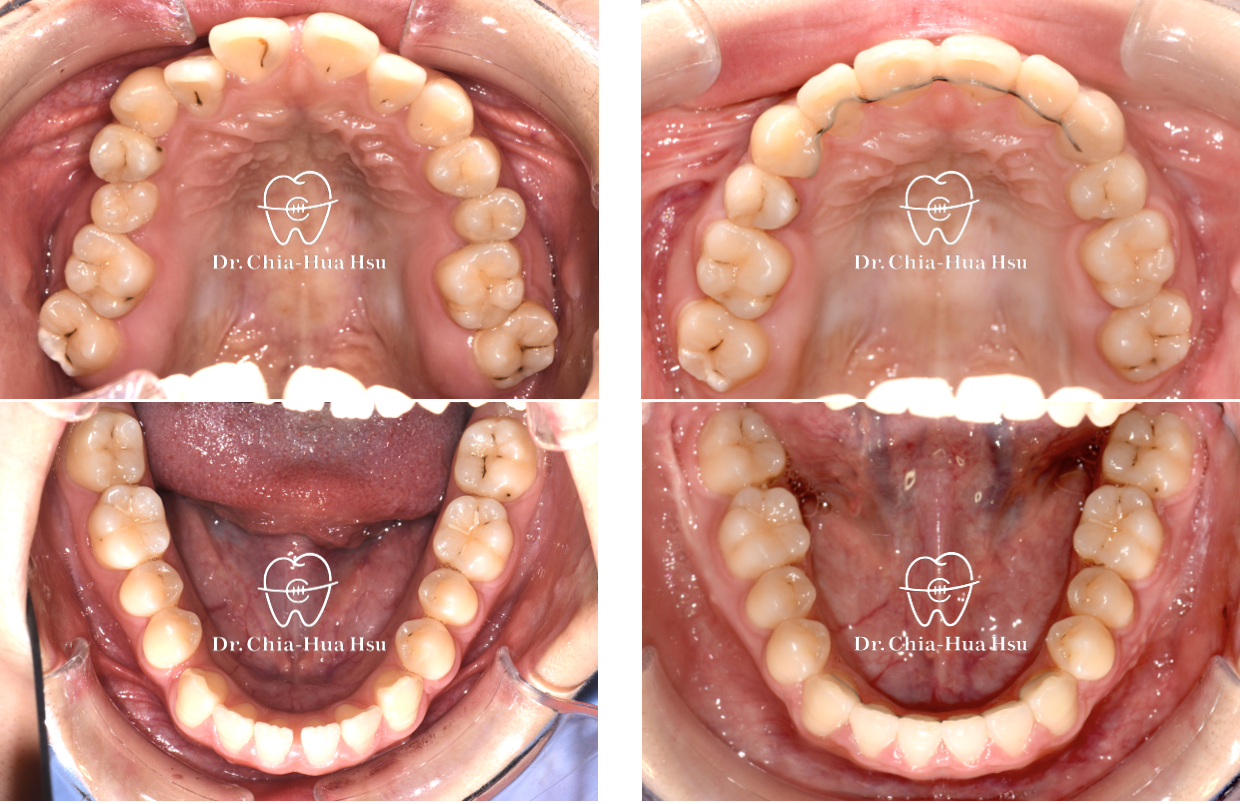

治療前

治療後

• 問題分析:患者是標準的骨骼三類咬合(Skeletal Class III),下巴明顯較長,還有上顎牙弓過窄、開咬以及齒列不正。

• 治療方式:使用傳統金屬矯正器,合併正顎手術(雙顎),上顎拔除兩顆小臼齒以利手術方式進行上顎牙弓擴寬。

• 治療結果:齒列排齊,咬合功能恢復,外觀更和諧。